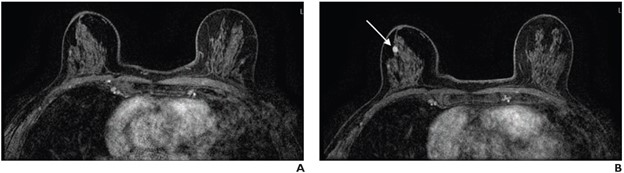

70-year-old-woman with extremely dense breasts. A. Axial subtracted contrast-enhanced fat-suppressed T1-weighted image from baseline AB-MR examination is negative (BI-RADS category 1). B. Axial subtracted contrast-enhanced fat-suppressed T1-weighted image from subsequent-round AB-MR examination performed 2 years later shows new 5-mm enhancing mass in upper outer right breast (arrow), which was not seen on mammogram performed 5 months prior. Examination was assessed as BI-RADS category 5. Ultrasound-guided core biopsy yielded invasive ductal carcinoma (ER+/PR+/HER2-).

Ultimately, in women with dense breasts, subsequent-round AB-MR for supplemental screening achieved lower AIR versus baseline rounds (7.8% vs. 17.4%, p <.001), while maintaining high CDR (12.1 vs. 18.9 per 1000, p =.37). All cancers diagnosed by subsequent round AB-MR were stage 0 or 1; had size of 0.3-1.2 cm; and exhibited node-negative status.